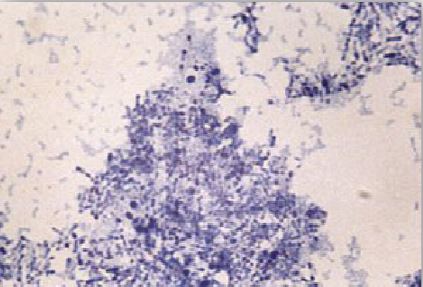

خلايا هذا النوع البكتيري هوائية وغير هوائية اختيارياً facultative anaerobs ولها القدرة على النمو في درجات حرارة ما بين 40-20 درجة مئوية وتعتبر درجة الحرارة 37 هي المثلى ، وهي موجبة لصبغة جرام وغالباً ما يكون الصبغ غير تساوي وباهت، كما أنها متعددة الأشكال والأطوال فتكون أحياناً عصوية وعلى هيئة مضرب الكرة club shape تتواجد في تجمعات ملتصقة بزوايا مختلفة بما يشبه الحروف الصينية . عند صبغتها بصبغة Neisser تظهر أجسام على الأقطاب (وهي عبارة عن عديد الفوسفات مخزنة في أحد الأقطاب). هناك 4 أنواع حيوية biovars وهم gravis وintermedius و mitis وكذلك belganti . وهذه الأسماء تستعمل لوصف شدة الإصابة ويتواجد هذا النوع البكتيري كفلورا طبيعية للقناة التنفسية العلوية والجلد.

مستعمرات النوع البكتيري C. diphtheria بصبغة جرام